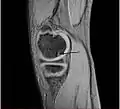

A large flap lesion in the femur head typical of late stage Osteochondritis dissecans. In this case, the lesion was caused by avascular necrosis of the bone just under the cartilage.